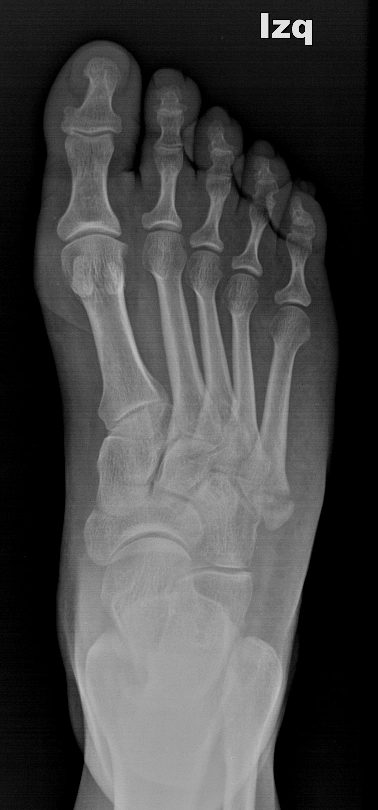

Gãy-trật Lisfranc (Gãy trật bàn chân)